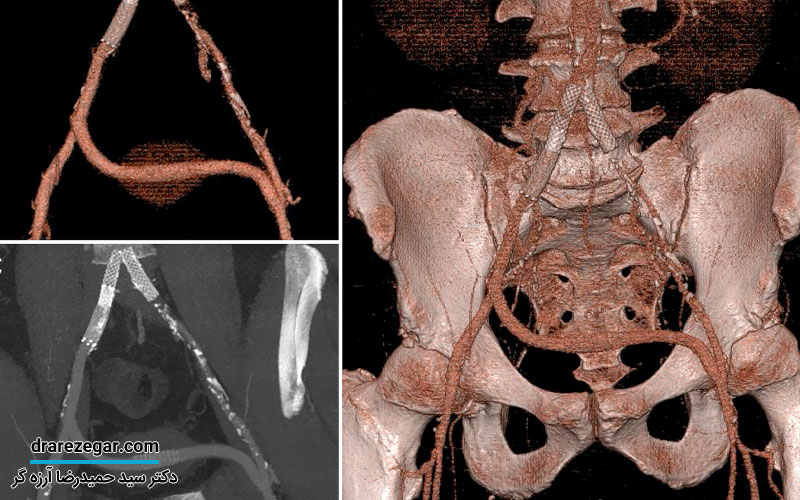

کسانی که با چنین علائمی همراه هستند؛ باید هرچه سریع تر توسط پزشک متخصص اورولوژی معاینه شوند تا علت آن تشخیص داده شود. سیستوگرافی، سونوگرافی، آزمایش ادرار و…چند نمونه از آزمایشات و تست هایی هستند که برای تشخیص این عارضه توسط متخصص اورولوژی انجام می شود.